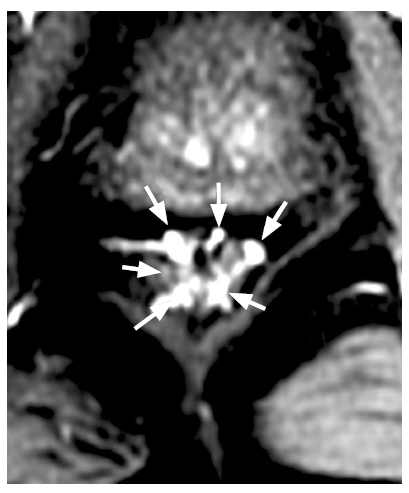

In all cases where interpretation was possible, six terminal branches of the superior rectal artery were identified, localized at 1, 3, 5, 7, 9, and 11 o’clock positions on the conventional dial (Fig. 2). Several anatomical variants of the upper rectal artery branching and its path to the rectal wall were revealed (Fig. 3 and Table 1). The superior rectal artery branches into three, with each branch subsequently splitting. This classical variant accounts for 54% of cases, as shown in Figure 3 (depicting the first, fifth, and sixth variants). Figures 4 and 5 are also included.

Fig. 2. Magnetic resonance tomography: 6 terminal branches of the superior rectal artery are visualized, located at 1, 3, 5, 7, 9 and 11 o`clock of the conventional dial.